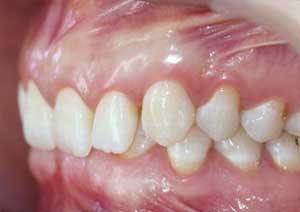

La supraclusion est définie comme le recouvrement excessif des incisives mandibulaires (inférieures) par les incisives maxillaires (supérieures).

Cliniquement, cela signifie qu’au sourire, le patient ne laisse pas apparaître les dents inférieures.

Il s’agit d’un problème de dimension verticale, fréquemment rencontré en pratique orthodontique quotidienne.

Avant